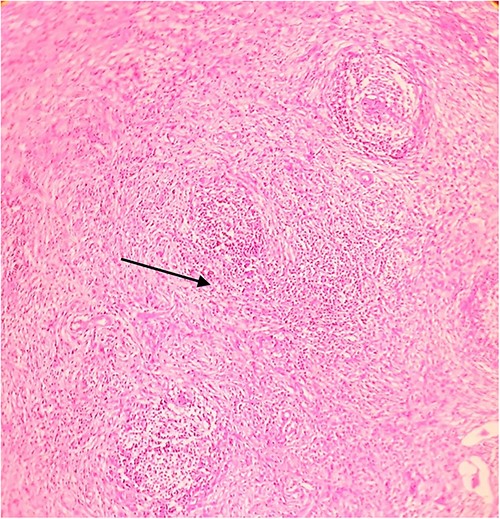

On laparotomy, the gastric antrum was infiltrated with a tumour with no serosal extension (Fig. 4), no ascites, and bilateral ovarian cysts (right: 12 × 10 × 6 cm, left: 9 × 5 × 4 cm) (Fig. 5). An R0 resection that included D2 gastrectomy and pan-hysterectomy was performed. The patient made an uneventful recovery and was discharged on the 15th postoperative day. The final diagnosis after histopathological examination was diffuse infiltrating gastric carcinoma signet cell-type (Figs 6 and 7), LP, KT deposits in both the ovaries (Fig. 8), with regional lymph node involvement (Fig. 9) in two nodes among the 15 nodes that were dissected. The staging was T4a, N1, and M1. The patient decided against adjuvant treatment. She was disease-free on clinical and radiological examinations at 12 months.

Postoperative histopathology H&E stain: 10× magnification of a representative perigastric lymph node showing tumour (arrow head) surrounding the germinal centres (arrow).